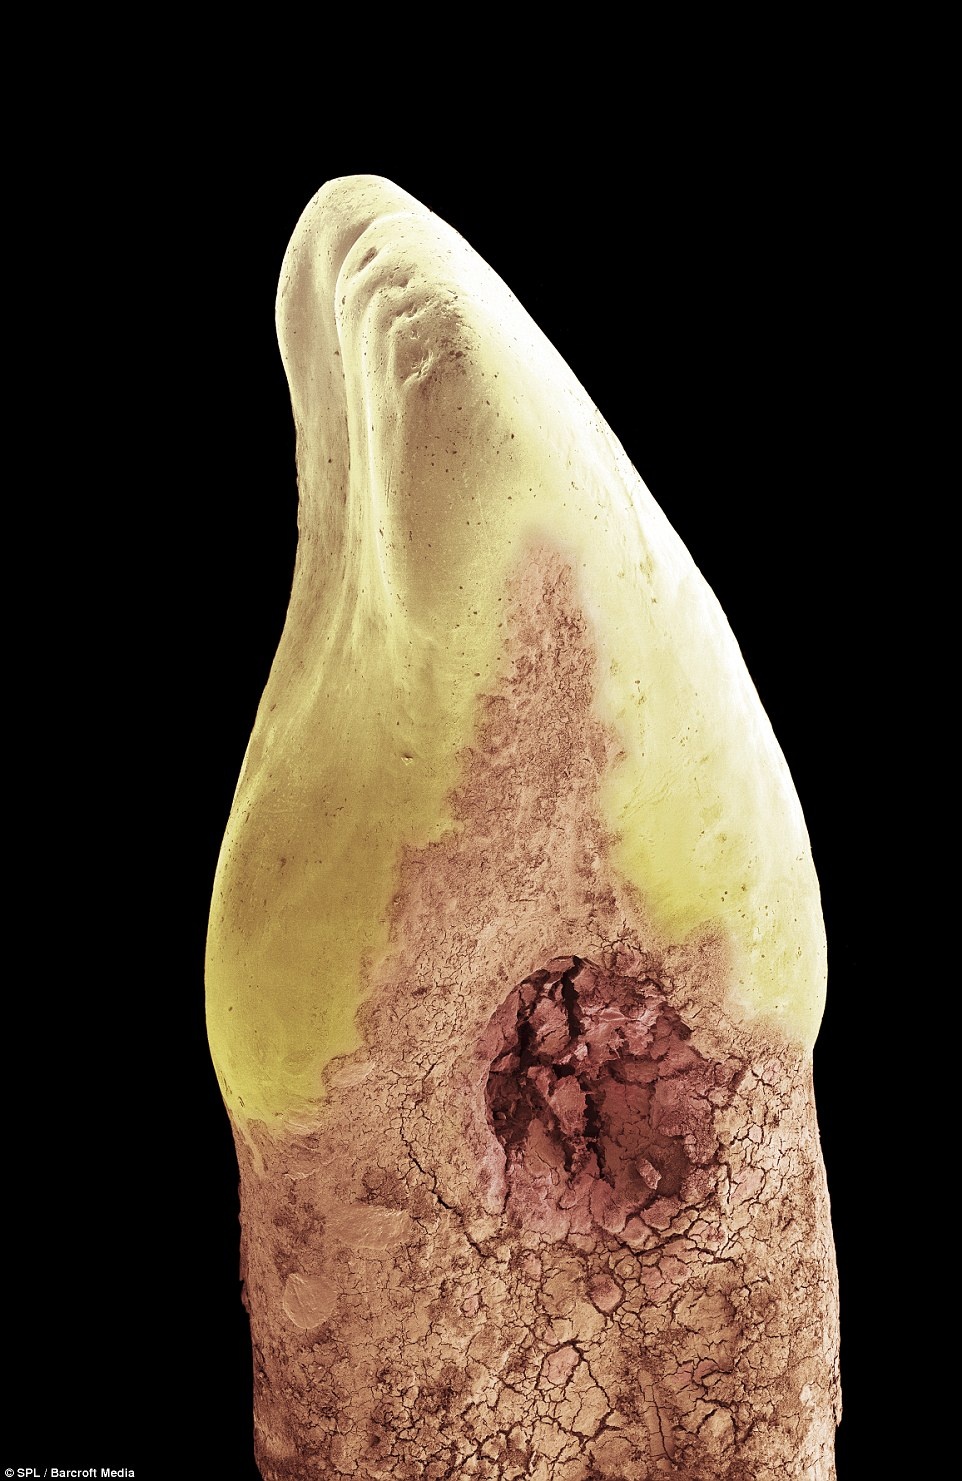

Ảnh chụp một chiếc răng sữa phóng to, phần chân răng đã bị vi khuẩn phân giải, chỉ còn lại phần mũ của răng. |